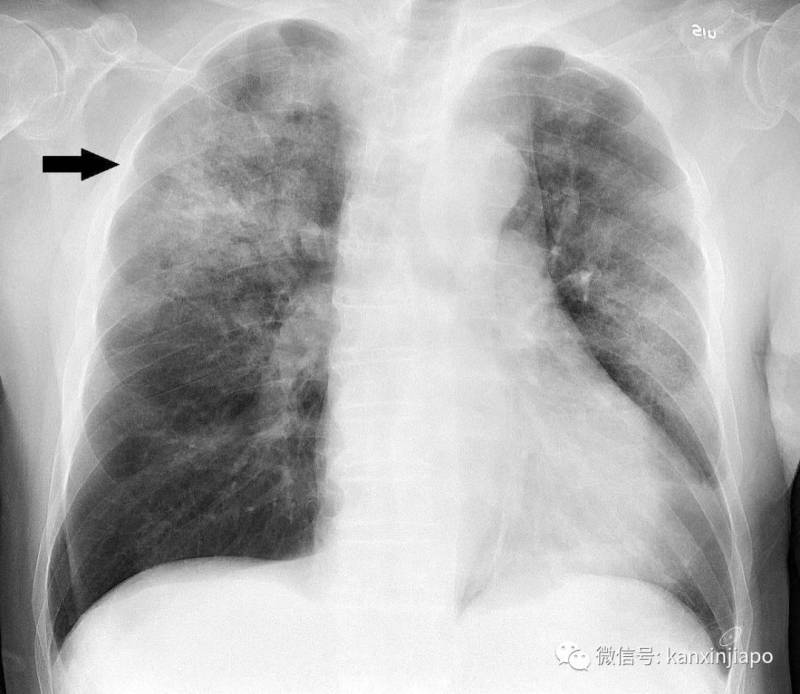

近日,中国湖北省武汉市爆出不明原因肺炎疫情,引发全球关注。

目前,中国武汉确证感染人数为44例,其中重症11例,其余患者生命体征总体稳定。